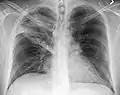

A chest X-ray showing a very prominent wedge-shape bacterial pneumonia in the right lung